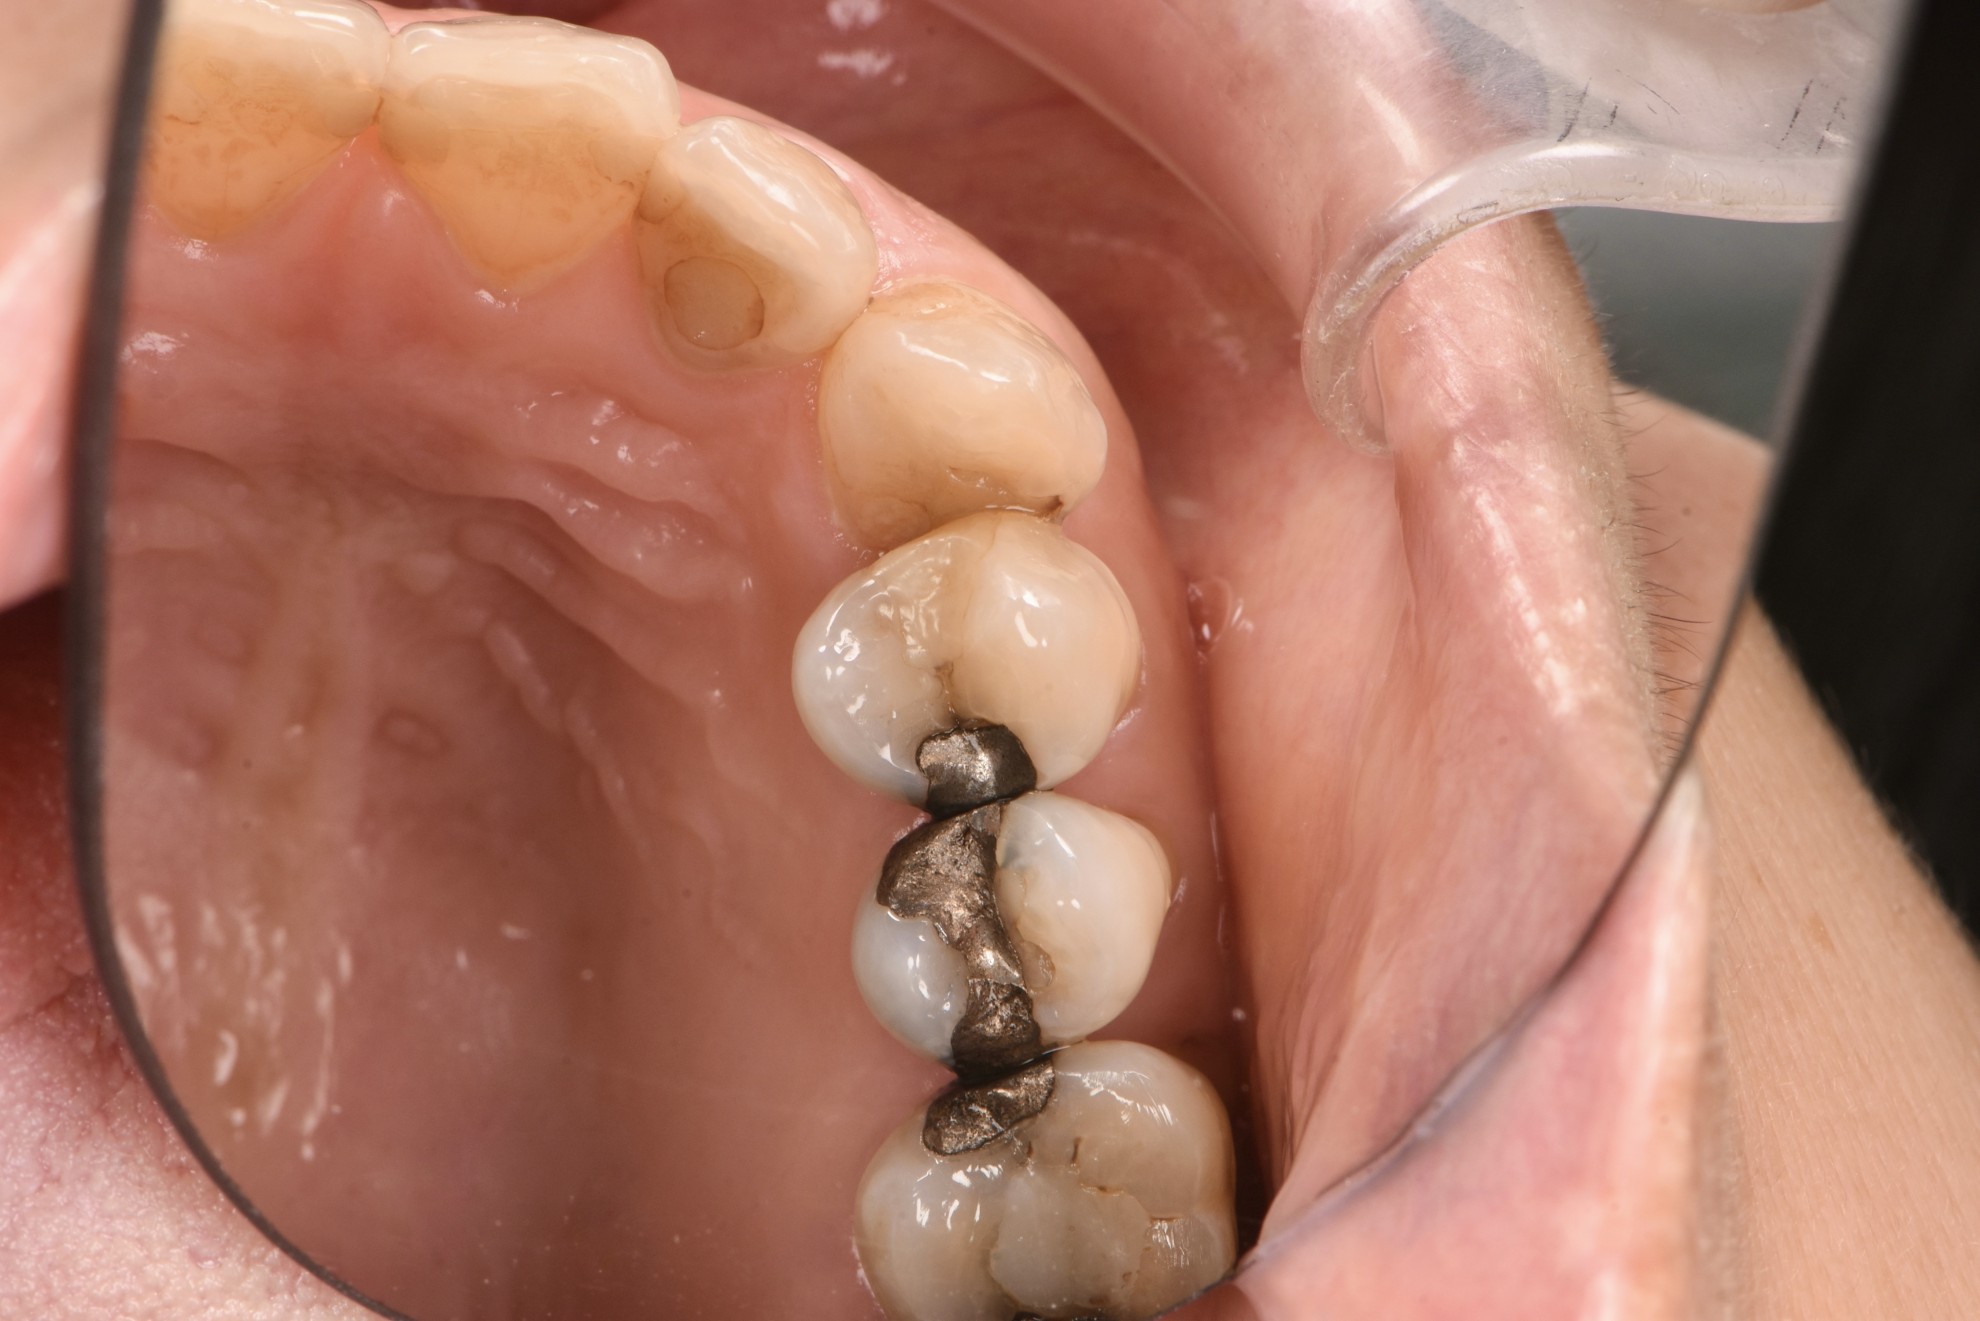

治療前

案例一